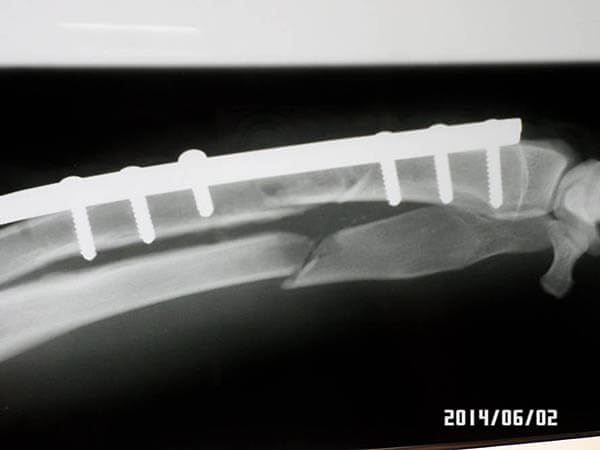

Am 2.6.14 wurde Ghost operiert! Wir hoffen auf schnelle Genesung und danach auf ein Zuhause!